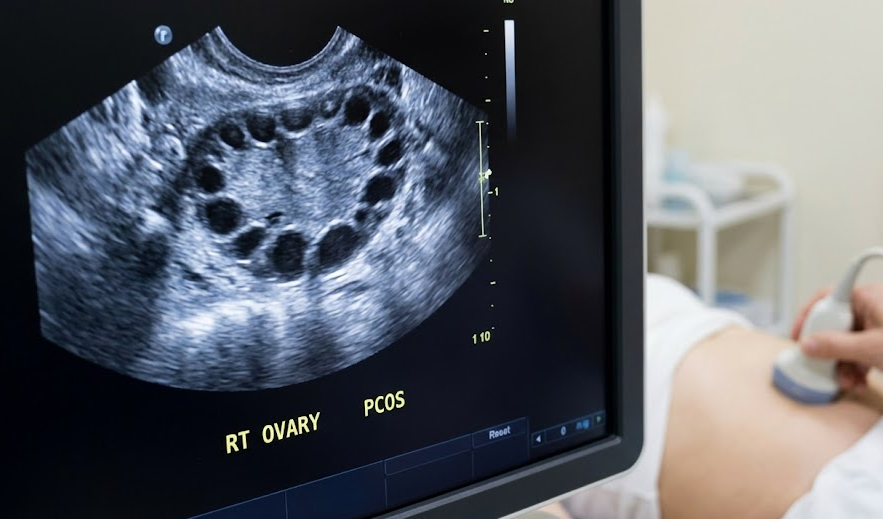

3. 2단계: 골반 초음파 검사 (눈으로 확인하기)

가장 핵심적인 검사 중 하나예요. 질 초음파(성경험이 없는 경우 항문이나 복부 초음파)를 통해 난소의 모양과 자궁 내막의 상태를 직접 확인해요.

- 무엇을 보나요?: 정상 난소와 달리 다낭성 난소는 2~9mm 크기의 작은 난포들이 염주처럼 동그랗게 줄지어 있는 모습(Necklace sign)을 보여요. 한쪽 난소에 이런 미성숙 난포가 12개 이상 보이거나, 난소의 부피가 10mL 이상으로 커져 있다면 다낭성을 의심할 수 있어요.